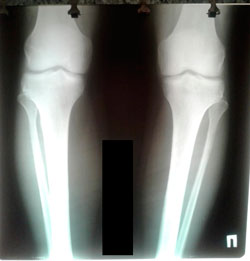

Исходник - 29 лет.

Дата операции - 29.09.2020

Мальчик